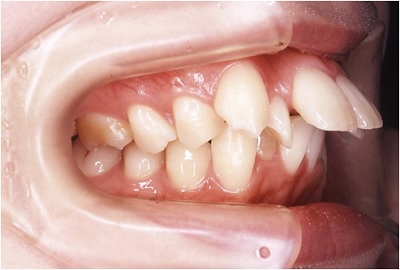

出っ歯の写真

上の前歯が下の歯よりも突き出ている状態は、一般に出っ歯、または過咬合と呼ばれます。